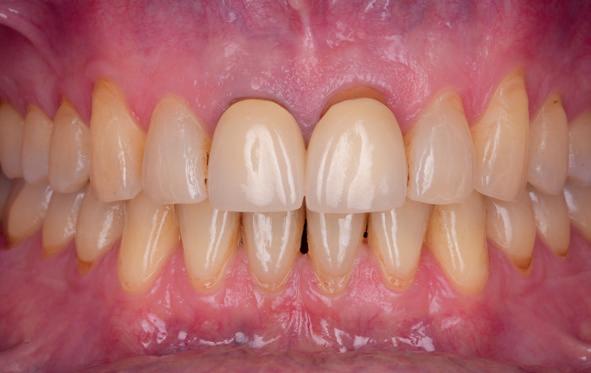

Esthetiek in de tandheelkunde, met name in het front, is een samenspel tussen de roze zachte weefsels en de witte harde weefsels. In het Engels wordt dit ook wel aangeduid met “pink and white esthetics”, waarbij het verkrijgen van correcte pink esthetics over het algemeen een grotere uitdaging vormt dan de white esthetics. Deze roze esthetiek is vooral van belang bij gebitselementen waarbij sprake is van recessie (het terugtrekken van de gingivalijn, waardoor de radix en een langere tand zichtbaar worden). De situatie wordt nog uitdagender wanneer een tand of kies niet is aangelegd, of in het verleden is verwijderd. Het element zorgt er immers voor dat de gingiva rondom de natuurlijke kroon ligt en dat er voldoende weefseldikte rondom deze kroon aanwezig is. Als het element ontbreekt, groeit het alveolaire bot dicht, omdat er geen radix meer is, en daarmee ook de mucosa (wanneer er geen element meer aanwezig is, spreken we niet meer van gingiva maar van mucosa), die dan afgevlakt is. De papillen tussen de afwezige elementen vlakken dan ook af.

Om één of meer afwezige elementen te herstellen bij een vaste voorziening, kan er een etsbrug of kunnen er implantaten worden geplaatst. De esthetiek valt of staat hierbij met de aanvulling van de zachte weefsels, zowel in de vorm van verbreding hiervan als het creëren van een zogenoemd emergence profile –dat wil zeggen dat de tand op een natuurlijk ogende wijze vanuit het tandvlees tevoorschijn moet komen.

Op 16-jarige leeftijd werd de patiënt door haar behandelend orthodontist naar de auteur verwezen voor een restauratieve oplossing voor de afwezige 11 en 21. In de tussenliggende periode had patiënt een retainer gedragen met twee kunststof tanden (afbeelding 1). Zowel de patiënt als haar moeder hadden een sterke voorkeur voor een implantaat gedragen vaste oplossing. Gezien haar jonge leeftijd was dit echter nog geen optie, omdat er nog verticale groei te verwachten viel. Implanteren op jonge leeftijd – dat wil zeggen vóór het 21e levensjaar – kan resulteren in een infrapositie van het implantaat, omdat de rest van het gebit nog verticaal kan doorgroeien.

Middels shared decision making werd het volgende plan overeengekomen: eerst zou er een etsbrug met vleugels op de 12 en 22 worden vervaardigd, om op 21-jarige leeftijd verder te gaan met implantologie.

18. Etsbrug frontbeeld

19. Etsbrug palatinaal